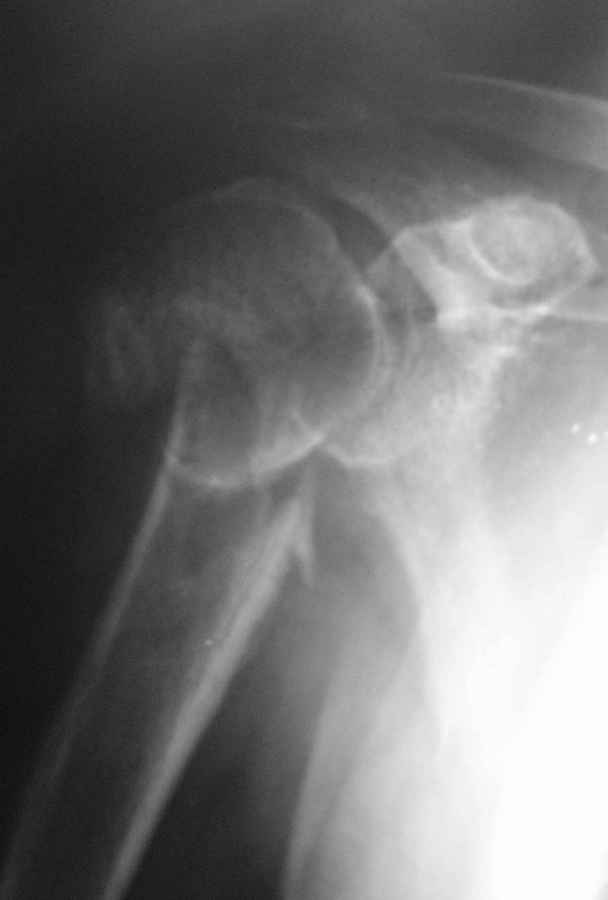

Перелом хирургической шейки плеча

Пациент 55 лет. травма 7.07.09г (первая Р-грамма). Лечился консервативно, надолго выпадал из под наблюдения леч. врача. Последний снимок от 7.08.09 г. Как видно на Р-грамме, стояние отломков неудовлетворительное, клинически выраженная патологическая подвижность. Соп. дз: сахарный диабет 1 типа, средней тяжести. Выскажите Ваше мнение о дальнейше тактике лечения данного пациента.